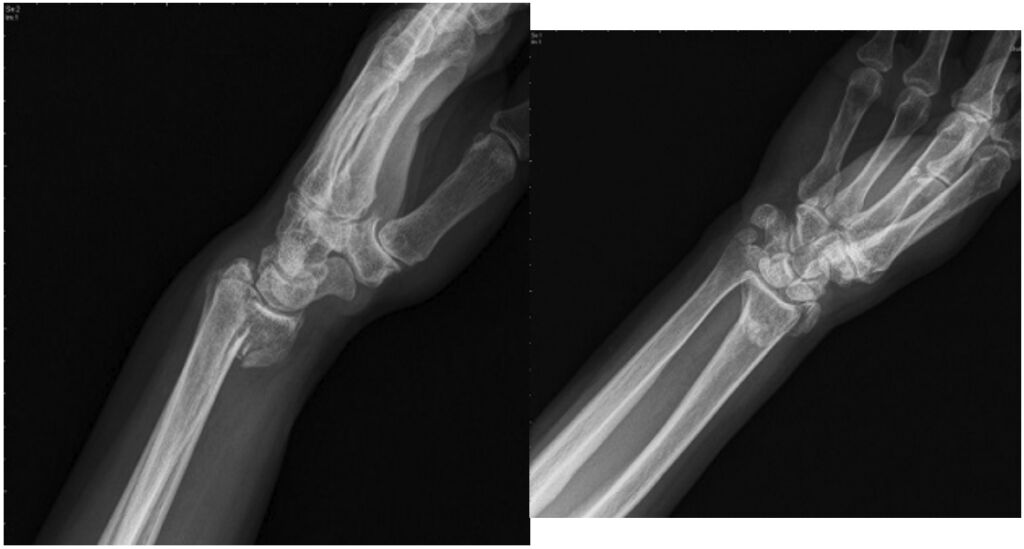

53.68歲女性2日前跌倒左手撐地,因左手腕腫脹瘀青無法用力而就診,X光如附圖所示,下列敘述何者正確?(A)跌倒時左手掌撐地造成 (B)該骨折又稱為反柯力氏骨折(Reverse Colles' fracture) (C)患者手腕外觀可見「餐叉樣」畸形 (D)此為伸直型骨折